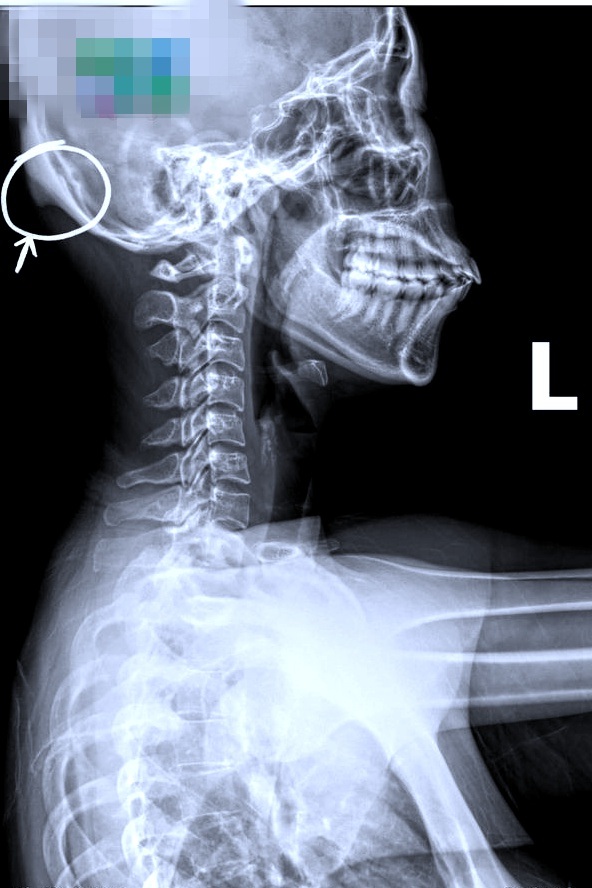

Sau khi khám và tiến hành chụp X-quang, chẩn đoán của bác sĩ khiến người phụ nữ choáng váng. "Mình đã thành "dị nhân". Xương sọ người bình thường sẽ tròn đều, còn V. thì mọc ra một "cái đuôi" siêu to, siêu rõ. Không phải do bẩm sinh mà phần đuôi này phát triển từ từ sau nhiều năm ngồi làm việc trên máy tính, cầm điện thoại sai tư thế" - người phụ nữ kể.

Ảnh chụp cho thấy sọ của bệnh nhân bị "mọc đuôi" phía sau (Ảnh: BSCC).